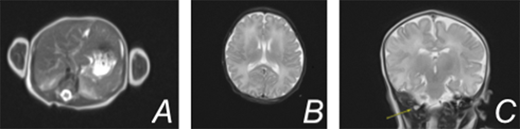

Case Description: A term female infant was born via scheduled c-section to a 32 year old G2P1000 mother who had been receiving weekly IVIG during this pregnancy due to the death of her first child at 4 days of life. Autopsy of that female baby demonstrated extensive neuropathological changes, liver steatosis, iron depletion, and ascites, consistent with GALD. Following delivery of our current patient, there was an elevated alpha-fetoprotein (greater than 80,000), decreased fibrinogen, and coagulopathy with peak international normalized ratio of 1.6. The patient received fresh frozen plasma and IVIG on day of life 1 with improvement of these levels. Complete blood count, liver function tests, and ammonia were within normal limits. An MRI of the liver demonstrated normal size, morphology, and normal iron levels based on T2 relaxometry. A buccal biopsy did not demonstrate extrahepatic iron deposition. MRI of the brain showed significant stenosis of the right transverse and sigmoid sinus relating to dural venous sinus thrombosis. There was no evidence of parenchymal infarction and no evidence of iron deposition. At this time, enoxaparin was initiated. The patient was discharged home on day of life nine on enoxaparin therapy.

Image: (A) MRI liver showing normal appearance without evidence of hemochromatosis (B) MRI brain showing no evidence of iron deposition within the brain parenchyma (C) MRV head showing right transverse and sigmoid venous sinus thrombosis